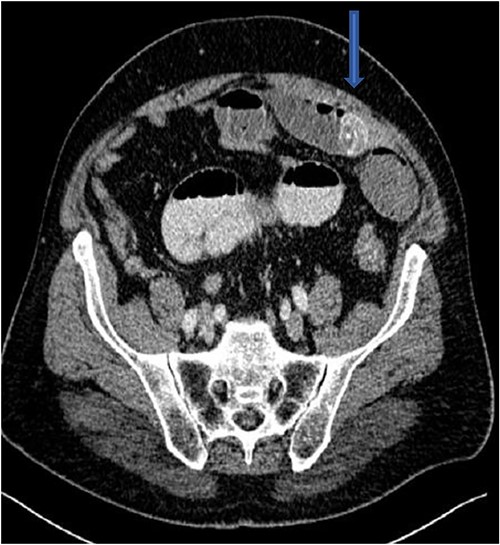

The plain film of the abdomen showed multiple air-fluid levels on the erect film (Fig. 1) and small bowel dilatation on the supine (Fig. 2). The CT showed multiple air pockets in the biliary tree, representing pneumobilia (Fig. 3). It also showed evidence of a circular radio-dense stone measuring 2 cm within the distal jejunum, leading to obstruction and dilatation of the proximal jejunum (Fig. 4).